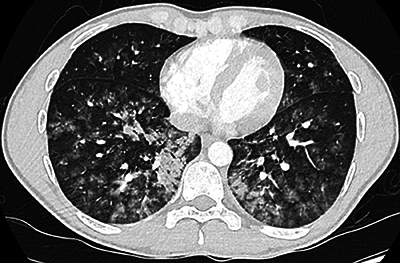

A case of complete recovery of negative pressure pulmonary edema after a Cottle surgery in a 24-year-old male. Teaching point: Negative pressure pulmonary edema is an important cause of postoperative noncardiogenic edema, with the spontaneous disappearance of all complaints within a relatively short period.

Abstract Image